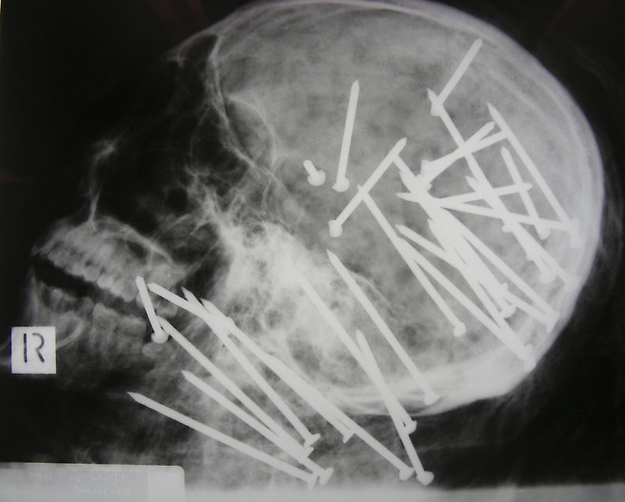

The skull of Chinese man who was shot in the head with a high-powered nail gun.